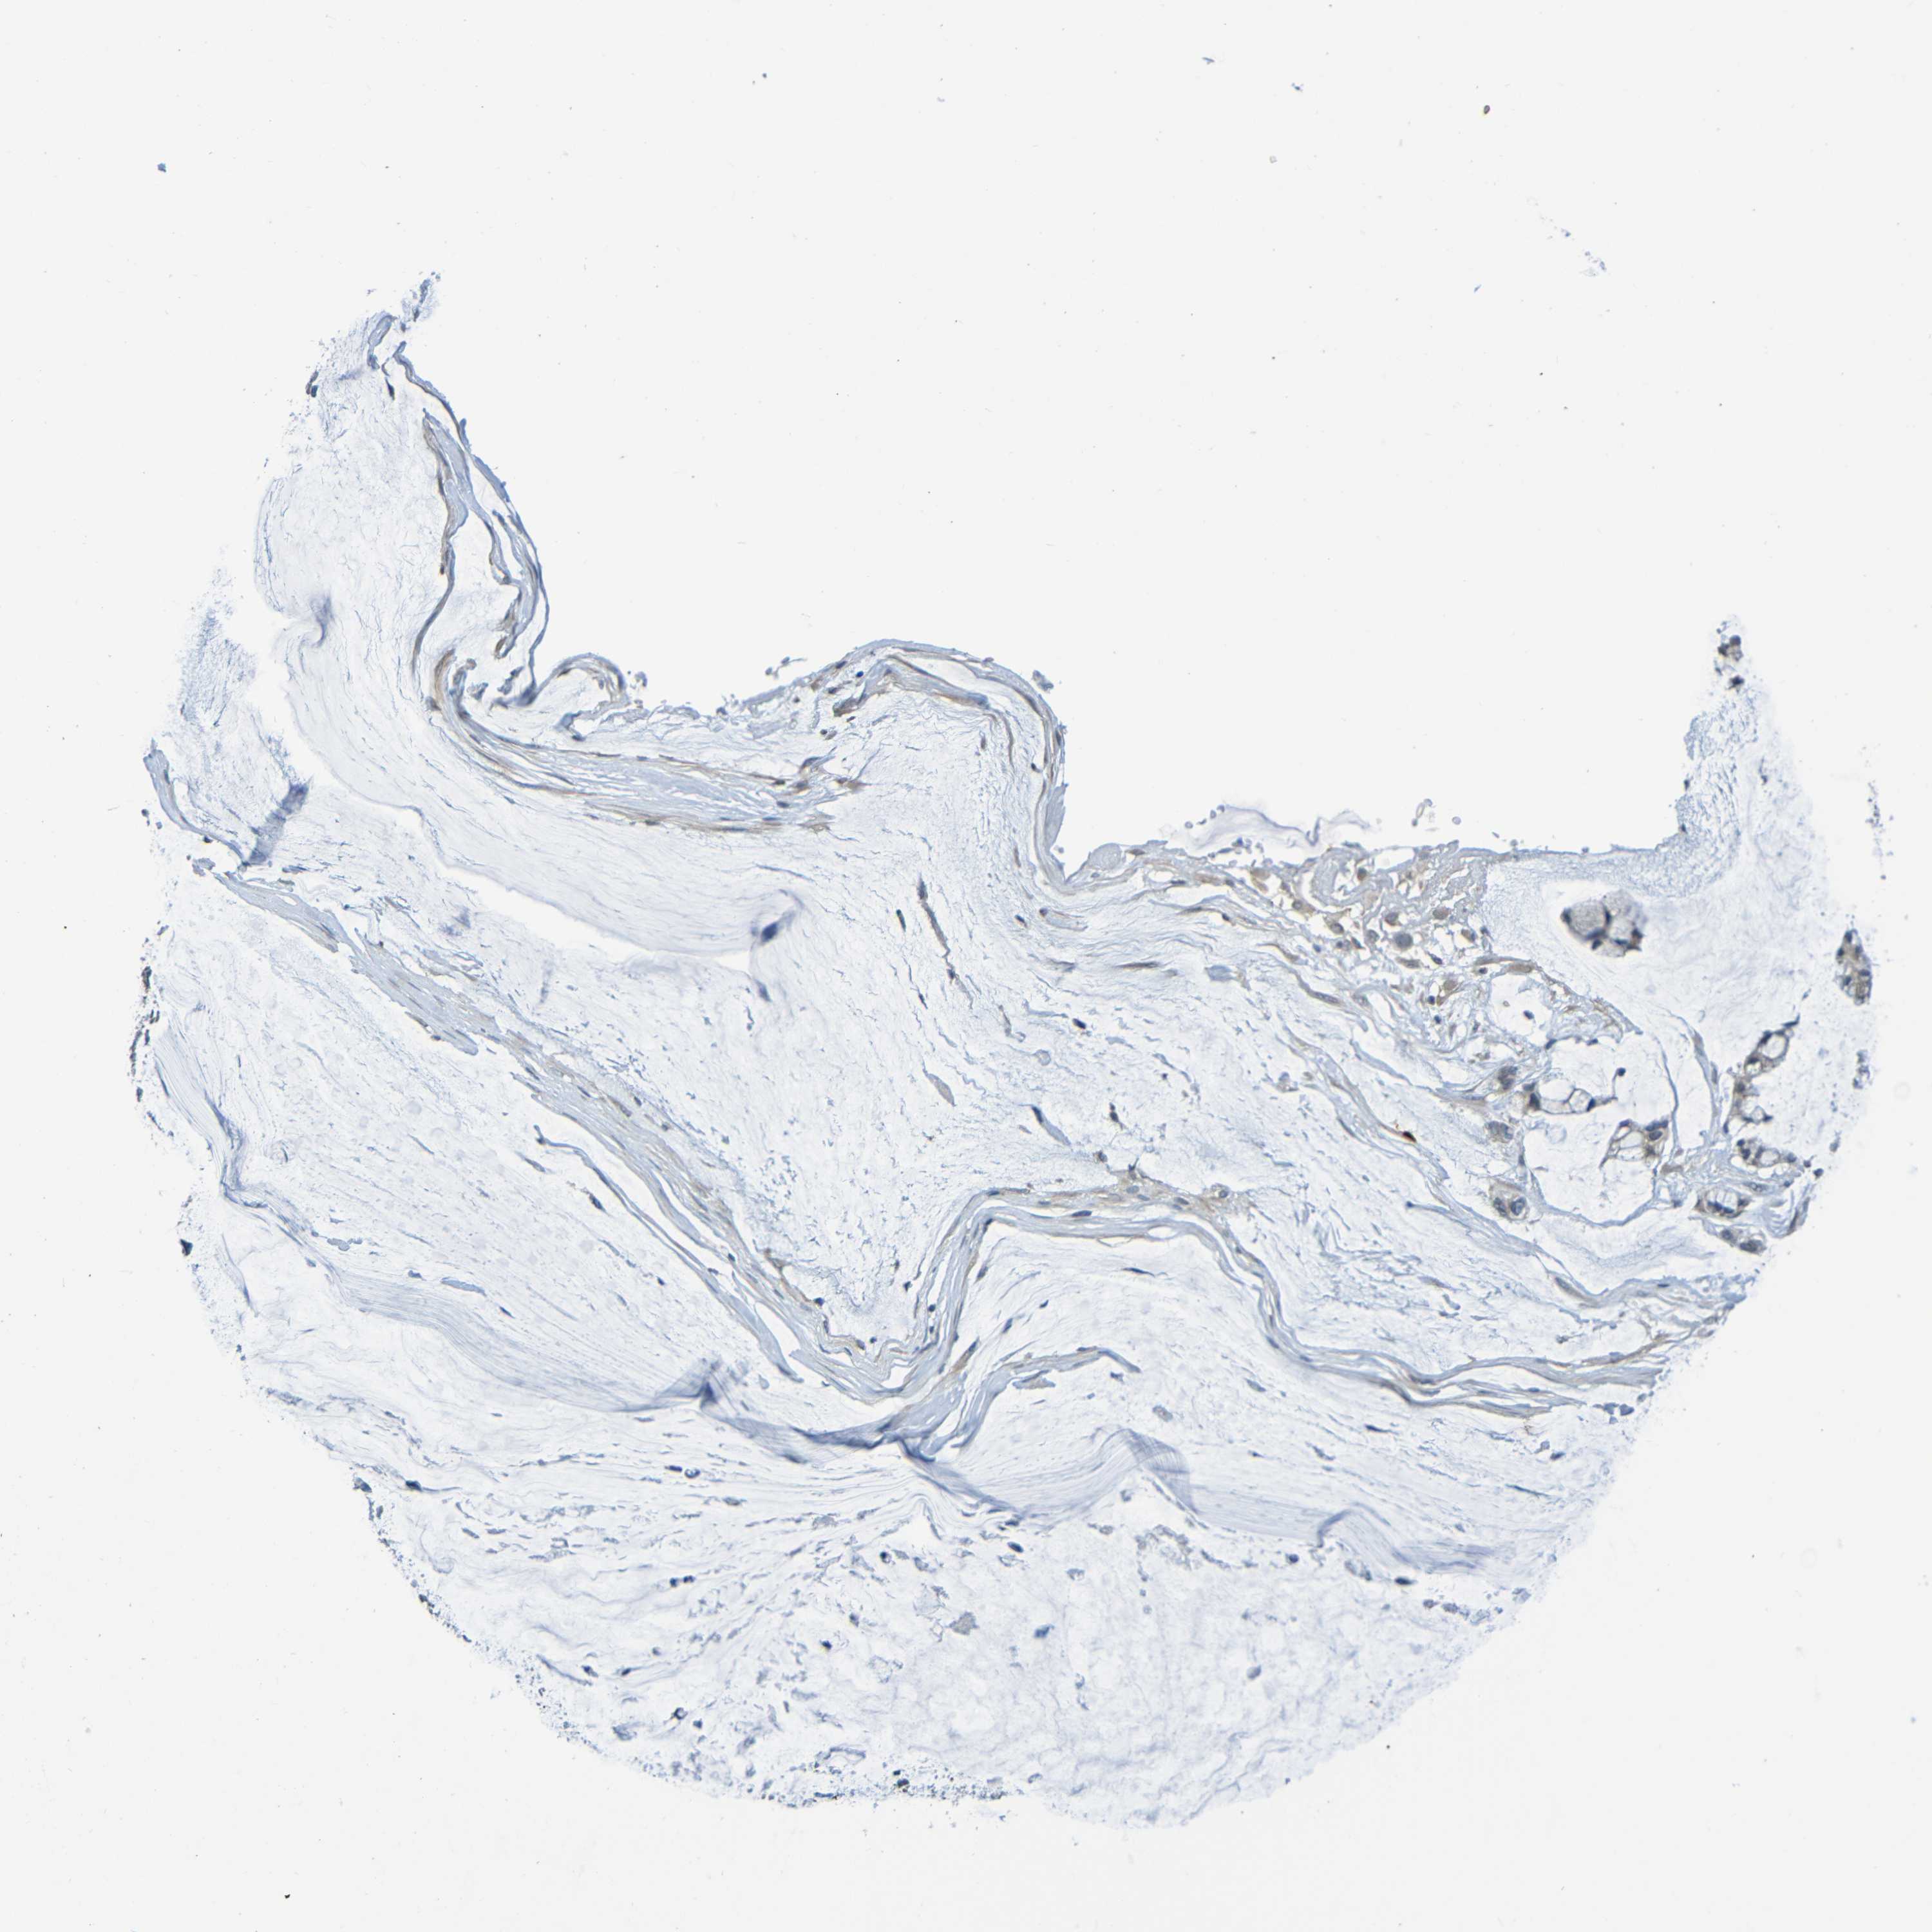

OVARIAN CANCER - Protein expressioni

A mouse-over function shows sample information and annotation data. Click on an image to view it in a full screen mode. Samples can be filtered based on level of antibody staining by selecting one or several of the following categories: high, medium, low and not detected. The assay and annotation is described here.

Note that samples used for immunohistochemistry by the Human Protein Atlas do not correspond to samples in the TCGA dataset.

Antibody stainingi

Antibody staining in the annotated cell types in the current human tissue is reported as not detected, low, medium, or high, based on conventional immunohistochemistry profiling in selected tissues. This score is based on the combination of the staining intensity and fraction of stained cells.

Each image is clickable and will lead to virtual microscopy that enables deeper exploration of all samples and also displays staining intensity scores, fraction scores and subcellular localization as well as patient and tissue information for each sample.

Antibody CAB009405

Staining

High

Medium

Low

Not detected

Intensity

Strong

Moderate

Weak

Negative

Quantity

>75%

75%-25%

<25%

None

Location

Nuclear

Cytoplasmic/membranous

Cytoplasmic/membranous,nuclear

Cystadenocarcinoma, serous, NOS

Carcinoma, endometroid

Cystadenocarcinoma, mucinous, NOS

Carcinoma, NOS